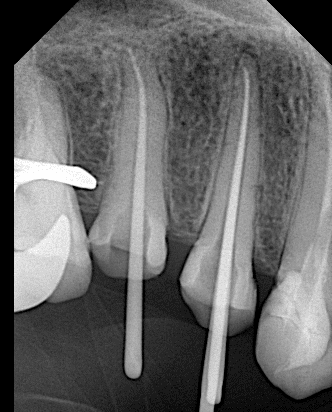

Cone fitt

After obturation

After preparation

Final x ray